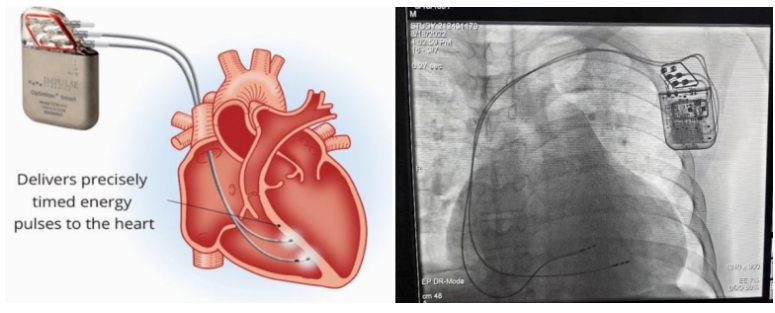

①植入式心臟復(fù)律除顫器

Implantable Cardioverter Defibrillator,ICD

植入式心臟復(fù)律除顫器是一種具有除顫功能的高級(jí)起搏器,是一種體積小、能植入患者胸部皮下組織的醫(yī)療設(shè)備。慢性心衰患者易發(fā)生室性心動(dòng)過(guò)速或心室顫動(dòng),導(dǎo)致心源性猝死(SCD)。ICD 則能在幾秒內(nèi)自動(dòng)識(shí)別并治療快速室性心律失常,通過(guò)低能量心臟轉(zhuǎn)復(fù)和高能量除顫等功能,顯著降低惡性室性心律失常引起的猝死風(fēng)險(xiǎn)。可及時(shí)自動(dòng)為患者轉(zhuǎn)復(fù)心律,通俗地說(shuō)就是裝在體內(nèi)的自動(dòng)除顫儀。

國(guó)內(nèi)研發(fā)企業(yè):無(wú)雙醫(yī)療、邁瑞、魚(yú)躍、久心、微創(chuàng)、維偉思、麥邦等

②心臟再同步治療

Cardiac Resynchronization Therapy,CRT

心臟再同步化治療,指雙心室起搏器,是通過(guò)雙心室同步起搏的方式,幫助心衰患者實(shí)現(xiàn)正常起搏的裝置。CRT包括一個(gè)口袋大小的脈沖發(fā)生器和三根電極導(dǎo)線,可被植入人體。通過(guò)監(jiān)測(cè)心律,在發(fā)現(xiàn)異常后,信號(hào)發(fā)生器發(fā)送電流脈沖,刺激心室重新同步,從而改善癥狀,提高患者的心臟泵血效率。目前有兩種類(lèi)型的CRT裝置:植入式心臟再同步治療起搏器(CRT-P)和植入式心臟再同步治療除顫器(CRT-D)。主要區(qū)別在于后者除了改善心臟收縮同步性外,還具備除顫功能,能及時(shí)處理危及生命的室性心律失常,避免猝死。

國(guó)內(nèi)研發(fā)企業(yè):無(wú)雙醫(yī)療、樂(lè)普醫(yī)療、先健科技、創(chuàng)領(lǐng)心律、秦明醫(yī)學(xué)等